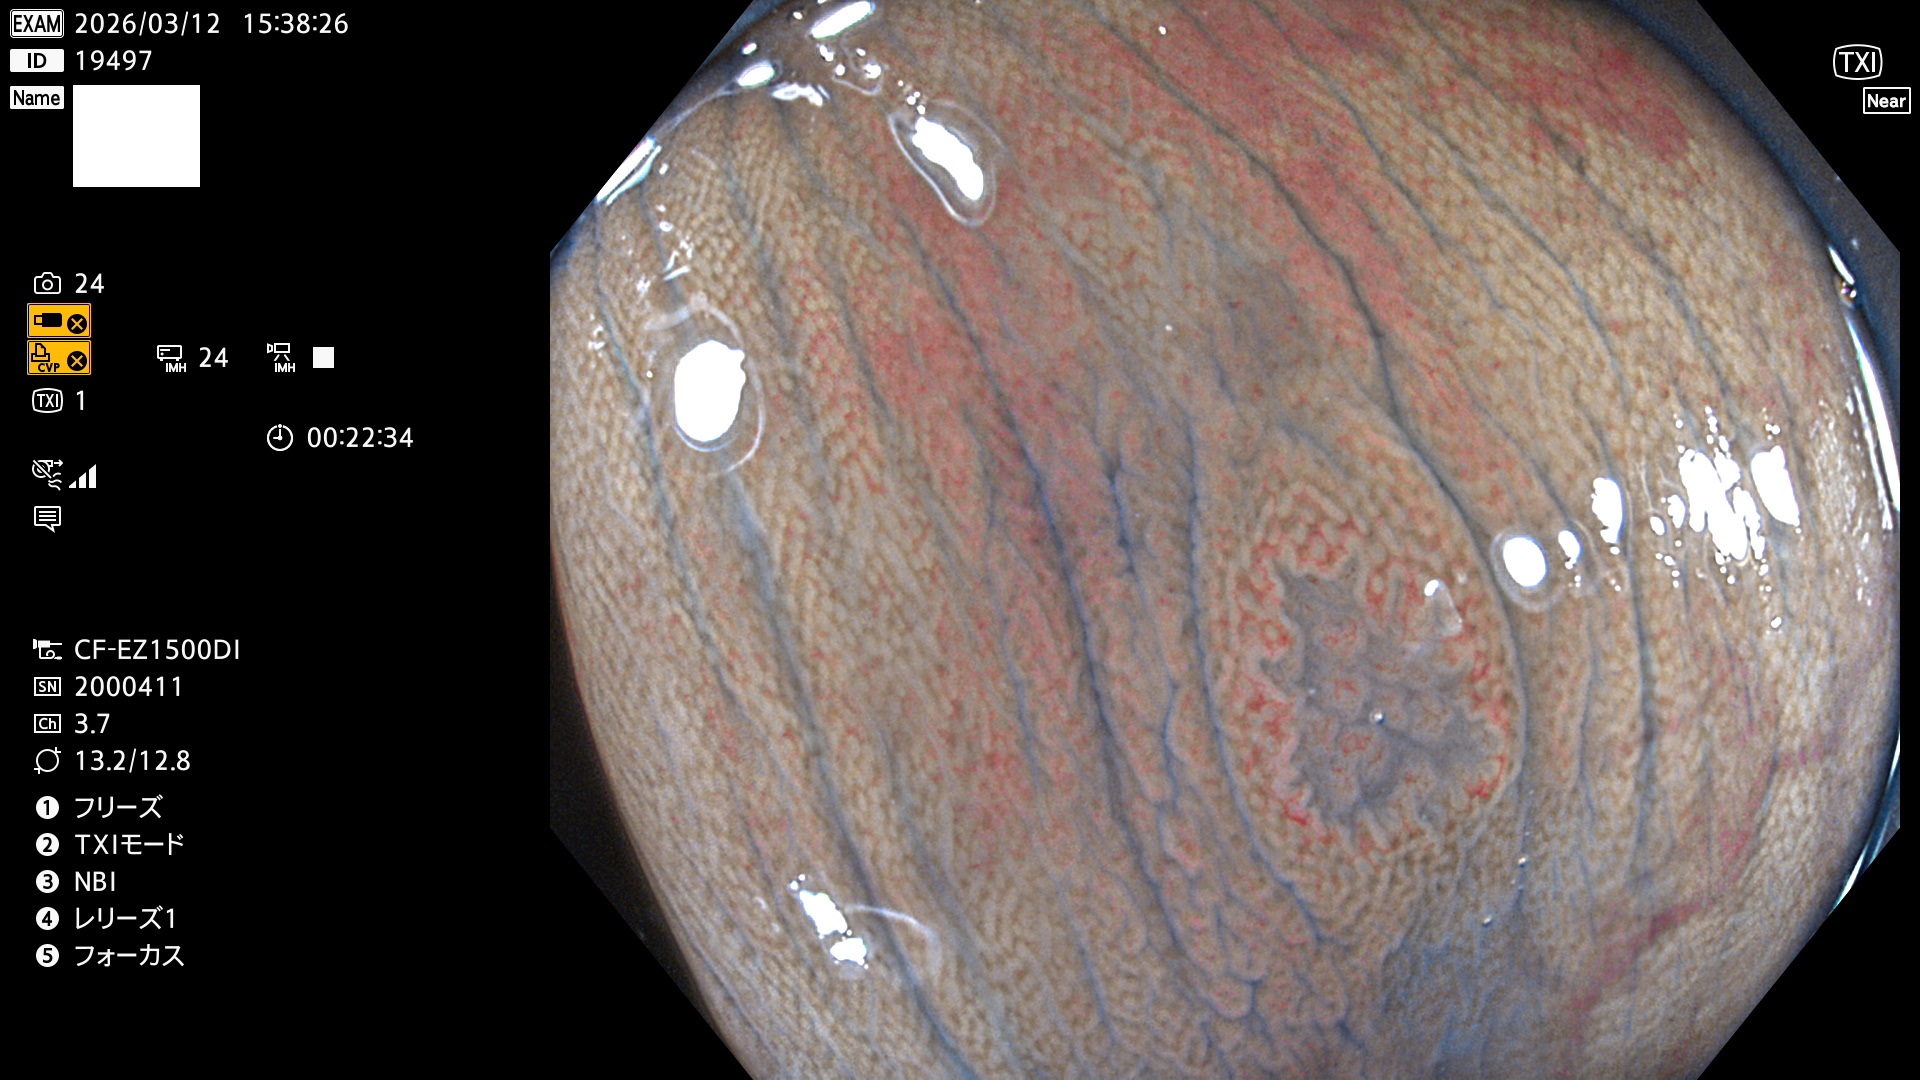

毎週の検査(木・金・土・日)に発見されたUbとUc型・腺腫を、その週の日曜の夜にUPし1週間、提示します。

2026年3月12日〜3月15日の4日間(40件)6個 (Uc_ADR=6個/40人=15%)